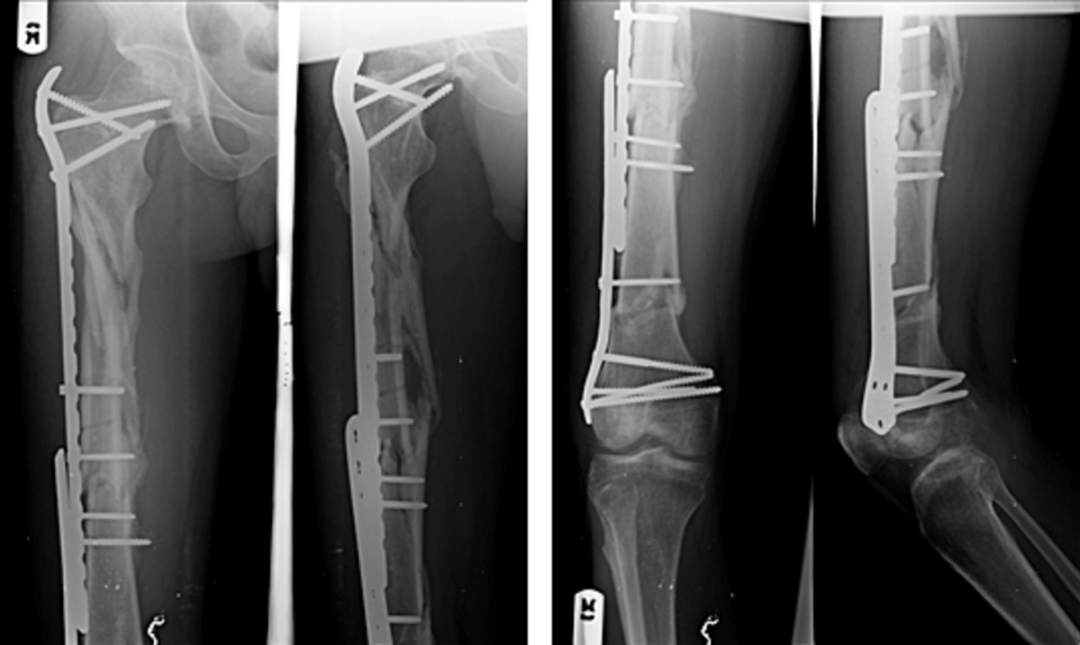

一,背景:复杂股骨骨折是指股骨干合并近端或远端骨折的复合型损伤,仅占所有股骨骨折的5%,治疗极具挑战性。单一内固定方案常难以实现有效固定,现有文献报道了多种治疗方式但疗效参差不齐。本病例报告展示了一例股骨近端严重粉碎性骨折合并远端节段性骨折的患者,其骨折极不稳定需手术治疗。据我们所知,此类复杂骨折类型在文献中极为罕见,关于其固定方式的报道几乎空白。本例采用微创双钢板重叠固定技术,分别于骨折区域上下方应用桥接型股骨近端锁定钢板与刚性股骨远端锁定钢板。二,案例:一名38岁男性患者因交通事故致右大腿闭合性损伤,表现为疼痛、畸形、肿胀及无法负重,至我院急诊就诊。患者为轿车后排乘客,车辆高速行驶时右侧遭受正面碰撞。查体见右大腿明显肿胀伴压痛。右大腿平片显示:右股骨近端节段性粉碎骨折合并远端两处横行骨折(图1)。采用微创钢板接骨术。经三个外侧切口显露股骨(图2)。采用间接复位技术,实现近端骨块的相对对位,并在透视引导下置入两块锁定钢板:股骨近端锁定钢板(PFLP)采用顺行置入,股骨远端锁定钢板(DFLP)采用逆行置入。两钢板重叠区域通过两枚皮质骨螺钉经对应孔道实现骨固定(图3)。术后给予镇痛药物、深静脉血栓预防及抗生素预防治疗,患者恢复顺利。引流管于术后第2天拔除,指导患者使用腋拐行走,右下肢禁止负重。术后第5天出院,嘱2周后返院拆线。在物理治疗师指导下,分别于术后6周及12周开始部分负重及完全负重行走。术后即刻X线片显示内固定位置良好(图4)。桥接钢板固定的近端区域可见四皮质骨痂形成,术后6个月(图5)及9个月(图6)X线片。远端节段性骨折线呈渐进性消失,术后9个月X线片显示骨折线完全消失(图6)。三,总结:此类复杂性股骨骨折属于罕见的高能量创伤。本文报道了采用微创双钢板接骨术成功治疗复杂股骨骨折的案例,结果显示骨折及时愈合且临床疗效良好。文献来源:Kabiru Salisu, Ifeanyi Kene Aghadi,Minimally invasive dual plating of a complex femoral fracture; a case report,Trauma Case Reports,Volume 43,2023,100768,ISSN 2352-6440, https://doi.org/10.1016/j.tcr.2023.100768.